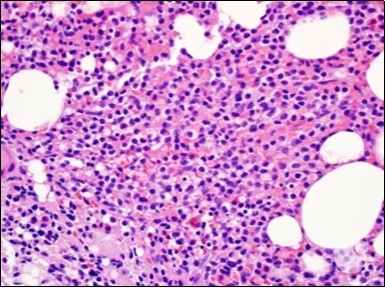

Figure 1.HCL: hairy cells infiltrating designated spaces(17).

The leukaemia cells may enunciate a characteristic immune phenotype, crucial for a confirmatory diagnosis. The peripheral blood mononuclear B cell population may display a kappa or lambda light chain restriction. The phenotype of classic hairy cell leukaemia may be delineated by concurrent, immune reactive CD19+ CD20+,CD 11c+, CD25+, CD103+ and CD123+. An intensely immune reactive CD200+ and a non reactive CD27- antigen may be present2, 4. Evaluation of a trephine bone marrow biopsy and bone marrow aspirate may define the degree of tumour infiltration. A dry tap on account of prominent bone marrow fibrosis may be elucidated at preliminary diagnosis. A decline in the normal haematopoiesis may account for a hypo-cellular marrow in 10% instances. Gradation of cellular infiltrating of the leukaemia within the bone marrow may be appropriately investigated with immune –histochemical stains2, 4. Immune staining for CD20+, annexin 1 and VE1 (a BRAF V600E stain] may validate the diagnosis and precisely analyse the extent of malignant bone marrow infiltration[8]. Determination of BRAF V600E mutation may be critical in therapeutically non responsive individuals with applicable standard therapy or in instances of multitudinous reoccurrences[9]. Deploying inhibitors of BRAF V600E gene may be efficacious in patients impervious to approved therapy. The mutation necessitates a comprehensive scrutiny of the implicated individuals with a sensitive molecular assay which may discern up to < 10% of the hairy leukaemia cells appearing in the peripheral blood smears or bone marrow aspirates diluted with peripheral blood or aspirates elucidating a dry tap[2,4]. Allele specific polymerase chain reaction (PCR) or a next generation sequencing may be optimally employed to circumvent false negative outcomes. If the leukaemia cells are sparse or if particularly sensitive & efficacious molecular techniques are not accessible, the application of appropriate immune histochemical stains to the bone marrow biopsy such as a BRAF V600E mutation stain (VE1) may detect the hairy cells and conclusively diagnose the condition[2,4,10]. Figure 1, Figure 2, Figure 3, Figure 4, Figure 5, Figure 6, Figure 7, Figure 8, Figure 9, Figure 10, Figure 11, Figure 12, Figure 13, Figure 14.

The classic hairy cell is medium sized with a magnitude of 10-14µm. The moderately abundant or variable cytoplasm may be transparent or mildly basophilic. The cellular surface with the characteristic serrated perimeter depicts innumerable fragile or stout extensions of cytoplasm ,particularly discernible on the phase contrast and electron microscopy. The cytoplasm may exhibit vacuoles with occasional azurophilic granules4. The nucleus may be elliptical or reniform, folded or indented with a coarse, reticulated or a finely dispersed chromatin and inconspicuous nucleoli along with infrequent mitosis. Bone marrow aspiration or bone marrow trephine biopsy may be inadequate for diagnosis in 30%-50% individuals4. The trephine sections of the bone marrow may depict a characteristic interstitial pattern of leukaemic infiltration. Generally the bone marrow is hyper-cellular, though it may be hypo-cellular in 10-15% individuals4. The leukaemia cell ingress may be diffuse or partial, although diffuse infiltration is frequent. The partial variety of leukaemic dissemination may be ineptly categorized with an indeterminate differentiation from the uninvolved marrow. The malignant insertions may initially emerge as miniature, undefined, cellular loci. The formalin fixed, paraffin embedded sections may elucidate a crystalline zone or a “halo” appearance of the cells with a circumscribed nucleus on account of the plentiful cytoplasm4. The cellular margins may be intertwined. Fixation of bone marrow smears with Zenker’s fixative may demonstrate a retracted cytoplasm of the hairy cells with a consequent disconnected structure. The bone marrow in the absence of a malignant process may be hypo-cellular or hyper-cellular. Reticulin stains may delineate an enhanced accrual of broad, dense reticulum fibres surrounding the aggregates of leukaemia cells with the fibrous circumlocution of individual malignant cell and fibrotic extensions into the abutting, uninvolved bone marrow4.